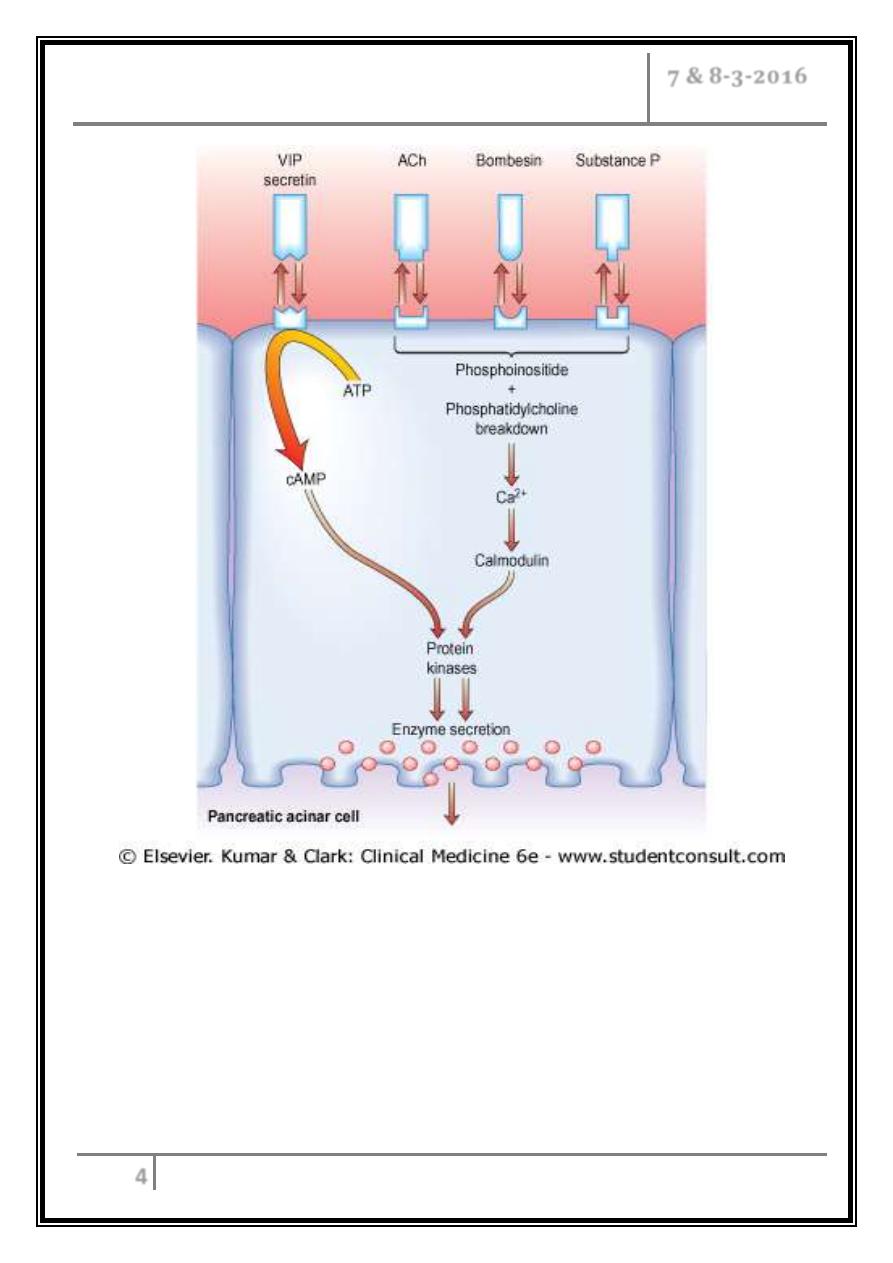

Diagram showing stimulus-secretion coupling of pancreatic cell protein

secretion. There is no CCK receptor in humans; stimulation is probably

via neural fibres. VIP, vasoactive intestinal polypeptide; CCK,

cholecystokinin; ACh, acetylcholine